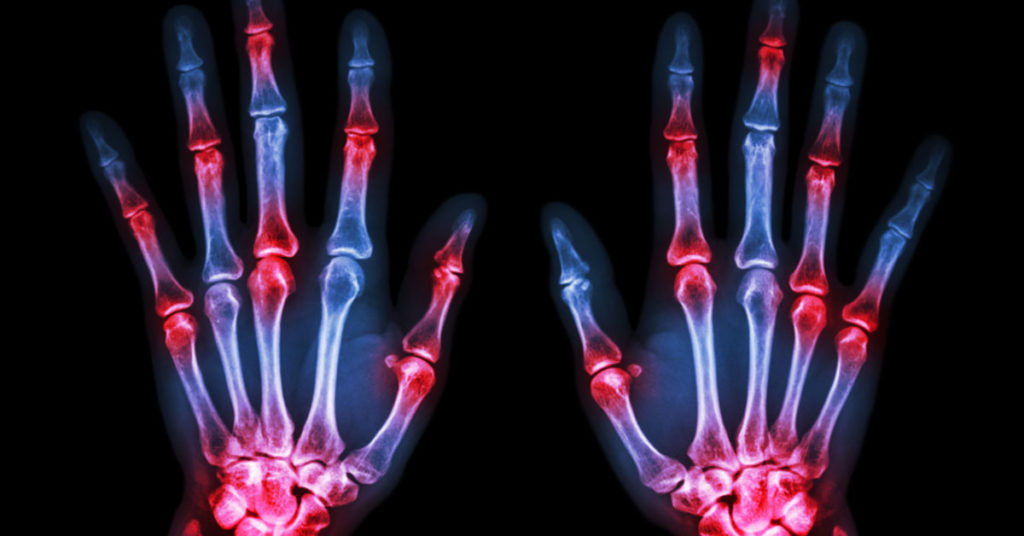

Arthritis is a complex disease with over a hundred different types. Generally, these are divided into two major categories: inflammatory arthritis, such as rheumatoid arthritis, gout, lupus, or fibromyalgia; and osteoarthritis, the most common form, which develops through wear and tear on the joints.

Osteoarthritis occurs when the cartilage, the body’s natural shock absorber that cushions the end of the bones in your joints, begins to deteriorate. When cartilage wears away sufficiently, the friction between your joints causes pain and stiffness. The joints most often affected are hips, knees, spine, and hands, but arthritis can affect any joint in the body.

Left untreated, arthritis can cause inflammation of the joint lining and the connective tissues that hold the joint together, leading to permanent joint damage. Inflammatory arthritis can lead to osteoporosis, a weakening of the bones that increases the risk of fracture. Adults with arthritis are more than twice as likely to fall, and to be more seriously injured in a fall, than people without arthritis.

Your doctor will determine the type of arthritis you have. Rheumatoid arthritis (RA), a common form of inflammatory arthritis, usually affects multiple joints, often on both sides of the body. Joints tend to feel warm and tender to the touch. Other symptoms, such as fatigue, fever, or loss of appetite, may indicate a more serious problem. RA can affects people at any age, even children, so a diagnosis should be followed by a consultation with a rheumatologist.